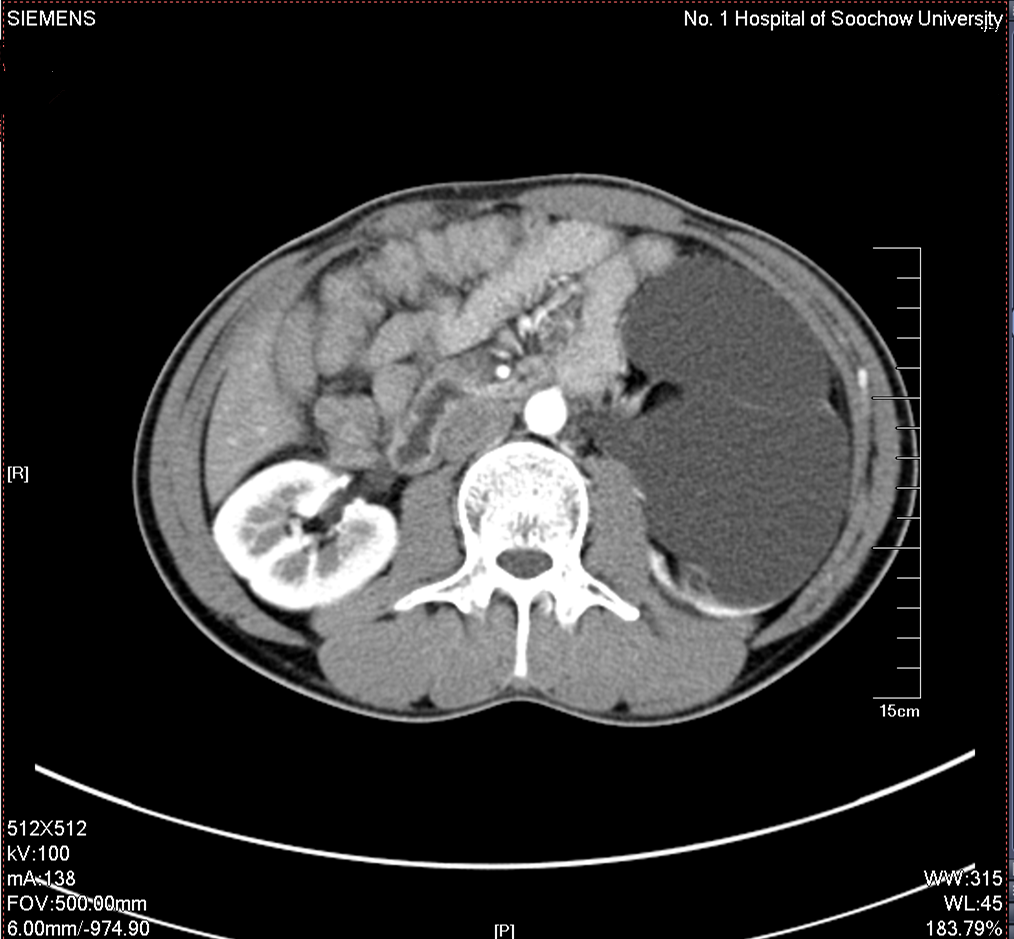

2016年04月手术患者,男性,37岁,盐城人,十七年前曾因左输尿管结石引起肾绞痛在当地予以多次震波碎石,疼痛缓解后未于重视,其间未予复查,一直于当地务农,自称今年来苏打工,招工体检时发现左肾重度积水一周来院求诊;CT:左侧肾脏重度积水,皮质菲薄,左侧输尿管结石约1.5cm,GFR:左侧4.89ml/min,右侧56.9ml/min。因右侧健肾代偿,肾功能正常:Cr 98umol/L;术前诊断:左输尿管结石 左肾重度积水 左肾无功能,鉴于左输尿管结石梗阻时间太长,左肾已几乎无功能,呈现皮囊肾样改变,最终只能行腹腔镜下左侧肾输尿管切除术,一并取出皮囊肾和输尿管及结石。

增强CT检查提示:左侧肾脏重度积水 皮质菲薄,几乎已无功能

左侧输尿管结石约1.5cm

GFR:左侧仅4.89ml/min,与增强CT检查相符